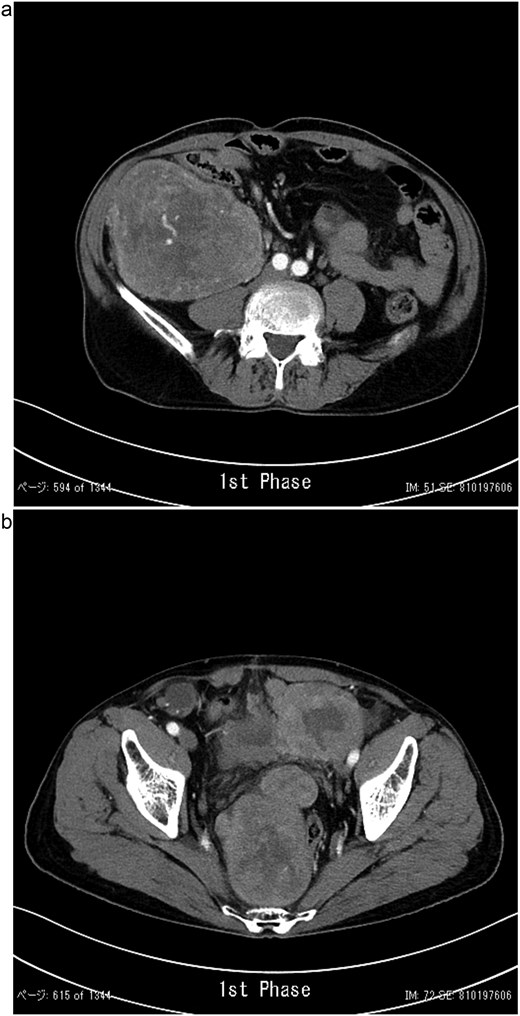

In 2011, a male patient in his 60s presented to the emergency department with loss of consciousness. His blood glucose level was 20 mg/dL. Contrast-enhanced computed tomography (CT) revealed a large tumour measuring 20 cm in diameter (Fig. 1). Primary surgery was performed and the tumour was diagnosed as an SFT histopathologically. Five years later, contrast-enhanced CT revealed a 4-cm tumour in the lower abdomen. His blood glucose levels were normal. A second surgery was performed; the tumour was excised, and several disseminated nodules were cauterized. Histology revealed that the tumour was an SFT. Eight years later, the patient presented with loss of consciousness. Laboratory data revealed a blood glucose level of 28 mg/dL. Contrast-enhanced CT revealed multiple tumours measuring 3–14 cm in diameter, spread within the abdominopelvic regions (Fig. 2). To prevent excessive intraoperative haemorrhage, preoperative TAE was performed on two larger tumours. Angiography revealed that the large tumour in the right lower abdomen was supplied by a branch of the superior mesenteric artery, whereas the pelvic tumour was supplied by branches from the inferior mesenteric and bilateral internal iliac arteries (Fig. 3). Super-selective catheterization and embolization of the vessels were performed. One week after embolization, a third surgery was performed. Nine tumours were resected. The operative time was 177 min, and the estimated blood loss was 620 mL. Histologically, part of the rectal wall showed necrosis. The tumour comprised spindle cells exhibiting a ‘patternless’ arrangement in a collagenous matrix (Fig. 4a). Immunohistochemical staining was positive for CD34, CD99, Bcl-2, and STAT6, which confirmed the diagnosis of recurrent SFT (Fig. 4b and c). The Ki-67 labelling rate was ~10% in the highly labelled regions. The tumour was also positive for insulin-like growth factor-II (Fig. 4d). After surgery, blood glucose levels completely stabilized. The patient developed a paralytic ileus that resolved spontaneously and was discharged 13 days after surgery. The patient was well, with no recurrence noted during the 10-month follow-up period.

Contrast-enhanced CT showing a lobulated, ill-defined mass with heterogeneous moderate enhancement in the right lower abdomen (a) and several masses occupying the pelvic cavity (b).